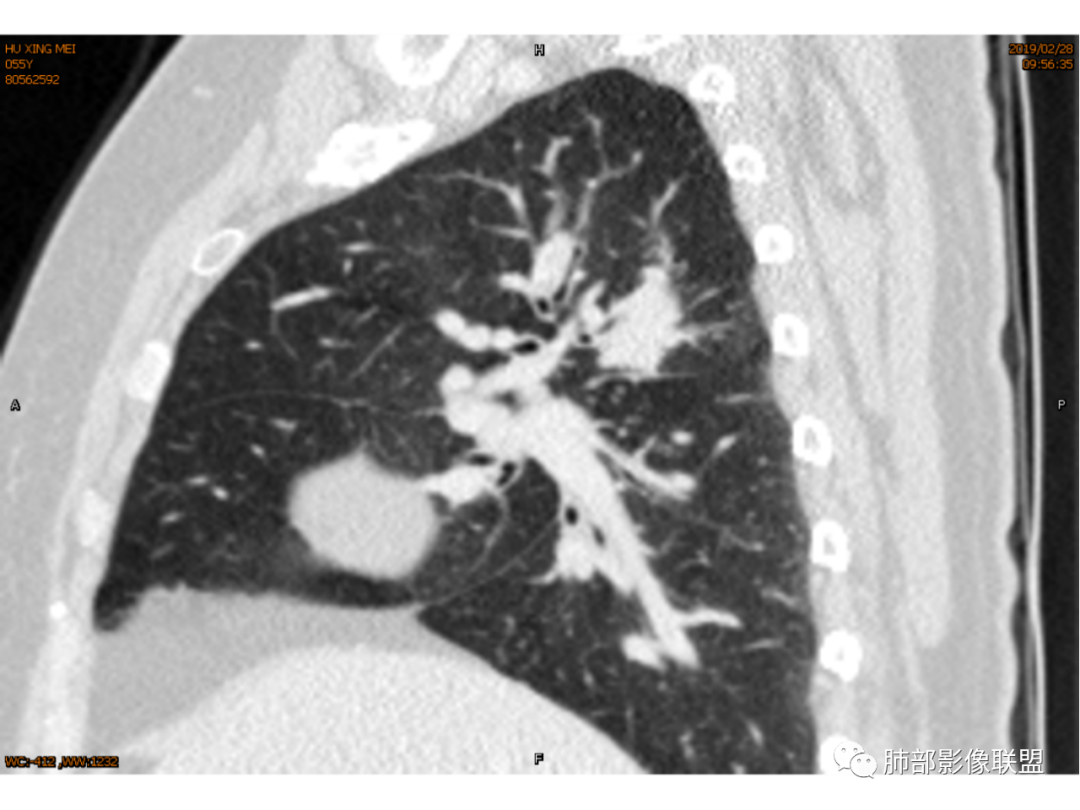

傅昌瑜:女性,咳嗽咳痰痰中带血1月。血常规、肿瘤标记物正常。CT:右上叶后段类圆形结节,内侧紧贴纵隔,前与右主支气管后壁分界不清。外后部分边缘平直收缩、矢状位可见U型凹陷、桃尖征,周围见边缘模糊的GGO,软毛刺。右上叶后段支气管似乎变狭窄。增强呈薄壁环形强化,内部强化不明显,强化时边缘似见有多个小结节与主病灶融合(芋艿子?)。远端见细小结节。整体考虑炎性病变,结核可能性大,注意鉴别腺癌。

右肺上叶肿块,靠近脊柱,类圆形,部分层面周围有晕,平直、凹陷、膨隆均有,水平位未见明显分叶,失状位重建有棘突/毛刺?局部叶间胸膜增厚,无明显牵拉僵硬,支气管通畅;中心无明显强化,周围环形强化影。临床:女性,亚急性病程,咳血。考虑:倾向良性,结核?

岁月:病史:咳痰血1月,右上叶占位,无发热盗汗;女,cea,角蛋白,nse正常影像:右上叶后段,后段支气管略窄,右肺门钙化,该处淋巴结成团,形态可辨认病灶边缘有钙化,周边高密度中间低,密度不均,芋艿子,中心44.6hu,边缘有强化,环状,应该较高。周边有点,平直,无毛刺,像棘角,有轻度牵拉毛刺软,血管推移。诊断:良性结节,结核。

1.女性,咳嗽咳痰痰中带血1月。血常规、肿瘤标记物正常。             2.CT示右肺上叶不规则肿块,边缘以平直收缩为主,可见U型凹陷及桃尖征,周围见边缘模糊的GGO,软毛刺,从形态学的角度病灶更支持炎性改变; 3.增强呈薄壁环形强化,壁光整、清楚,也支持炎性改变;病灶内部平扫CT值密度比较高,约40HU,明显高于水的密度,而且未见强化,提示病灶的坏死可能为凝固性坏死;    4.从上面的分析,病变更符合炎性,患者白细胞不高,治疗后没有好转,不支持普通细菌的感染;影像病灶较局限,边界较清楚,病灶慢性炎症或肉芽肿,形态机发病部位更符合继发性肺结核。患者非易感人群,病灶孤立,尽管有液化,也很难第一时间考虑真菌,尤其是曲霉菌感染。什么是炎性肉芽肿?炎性肉芽肿的常见疾病谱系有哪些?那什么是凝固性坏死和干酪样坏死?跟一般的液化性坏死有什么区别?接下来我们逐一学习一下。